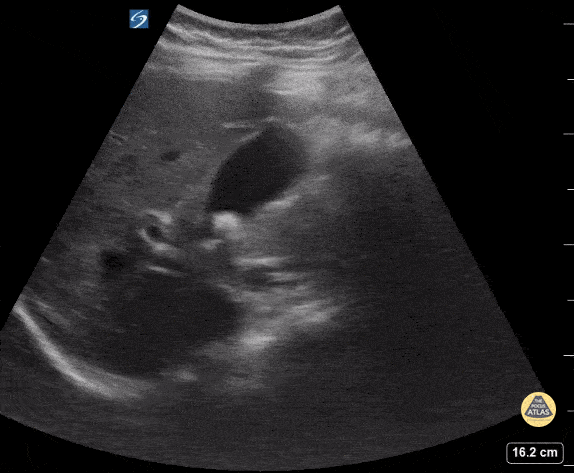

Peds-Biliary - Cholelithiasis with Stone in Neck

15 y/o M with RUQ pain, found to have cholelithiasis without cholecystitis. Contributor: Kathryn Pade, MD, Rady Children's Hospital San Diego